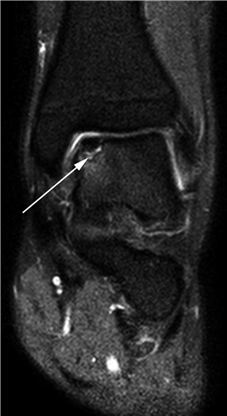

Weight-bearing anteroposterior (AP), lateral, and sesamoid axial radiographs are mandatory. On the AP view, the surgeon measures the Hallux Valgus Angle (HVA, normal < 15°), the Intermetatarsal Angle (IMA, normal < 9°), and the Distal Metatarsal Articular Angle (DMAA). The lateral view is scrutinized for Meary's angle (talo-first metatarsal angle) to identify midfoot collapse, as well as the presence of dorsal osteophytes indicative of hallux rigidus. The sesamoid axial view is critical for assessing the degree of sesamoid subluxation and the integrity of the crista.

Image

Avascular necrosis of the metatarsal head is a devastating complication primarily associated with distal osteotomies. It presents with insidious onset of pain, swelling, and eventual radiographic collapse of the articular surface. Prevention is paramount and relies on preserving the plantar-lateral soft tissue attachments during the lateral release. If symptomatic AVN occurs and progresses to joint destruction, the definitive salvage procedure is a first MTP arthrodesis, often requiring structural bone grafting to restore metatarsal length.